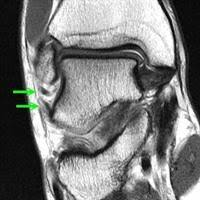

Essa variante é caracterizada por dor na região do corpo do tendão, e costuma ter início pela manhã, logo na primeira pisada, e piorar com a realização de exercícios. Entretanto, pode evoluir para quadros mais intensos, nos quais o paciente queixa-se de dor até em repouso. A ressonância magnética costuma demonstrar o processo inflamatório ou degenerativo no trajeto do “corpo” do tendão.

Figura 6: Imagens de ressonância, em corte sagital à esquerda e axial à direita. No corte sagital vemos o espessamento tendíneo e à direita vemos o corpo do aquiles arredondado e espessado.